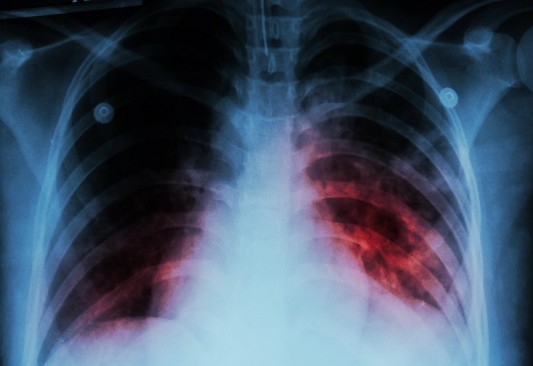

Tuberculosis sigue circulando, importante no confundirla con enfermedades respiratorias Piedras Negras • Publicado en 2022-12-20 Durante esta temporada en que se han incrementado las enfermedades respiratorias, la coordinadora...